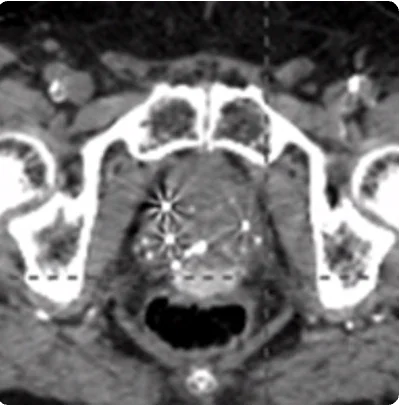

169cc prostate post-CT showing BioProtect Balloon Spacer, prostate, and rectum.

Post-CT

Image courtesy of Dr. Vishesh Agarwal, Radiation Oncologist.